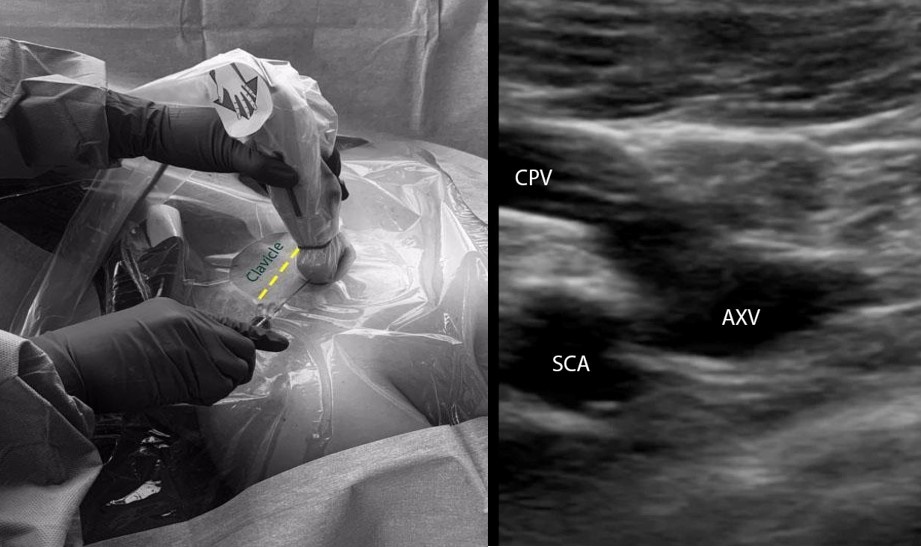

A. Infraclavicular in-plane approach (Figure 2):

- Place a linear transducer (6-13 MHz) in the infraclavicular fossa, approximately 2-3 cm distal to where the SCV courses below the clavicle.

- Obtain a long-axis view of the axillary vein and the distal SCV. Evaluate the depth, caliber, and patency of the axillary vein and the SCV.

- Use compressibility and/or pulse-wave Doppler to confirm that the structure visualized is indeed the vein, and not the artery.

- Insert the needle in the midpoint of the small footprint transducer using the in-plane approach. The needle should be advanced slowly, taking note of the lung pleura underneath the vessels.

- If needle visualization is lost, it is important to stop advancing the needle. Withdraw slightly and re-visualize the needle before proceeding.

- Once within the lumen of the vessel, insert the guidewire and monitor the guidewire placement in real time with ultrasound.

- Make a small incision on the skin, dilate the vessel, and insert the catheter over the guidewire.

Figure 2: Ultrasound-guided subclavian vein cannulation. AXV (axillary vein), SCA (subclavian artery), SCV (subclavian vein).